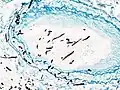

Pulmonary invasive aspergillosis in a person with interstitial pneumonia (autopsy material), using Grocott's methenamine silver stain | |

On microscopy, Aspergillus species are reliably demonstrated by silver stains, e.g., Gridley stain or Gomori methenamine-silver.[27] These give the fungal walls a gray-black colour. The hyphae of Aspergillus species range in diameter from 2.5 to 4.5 μm. They have septate hyphae,[28] but these are not always apparent, and in such cases they may be mistaken for Zygomycota.[27] Aspergillus hyphae tend to have dichotomous branching that is progressive and primarily at acute angles of around 45°.[27]